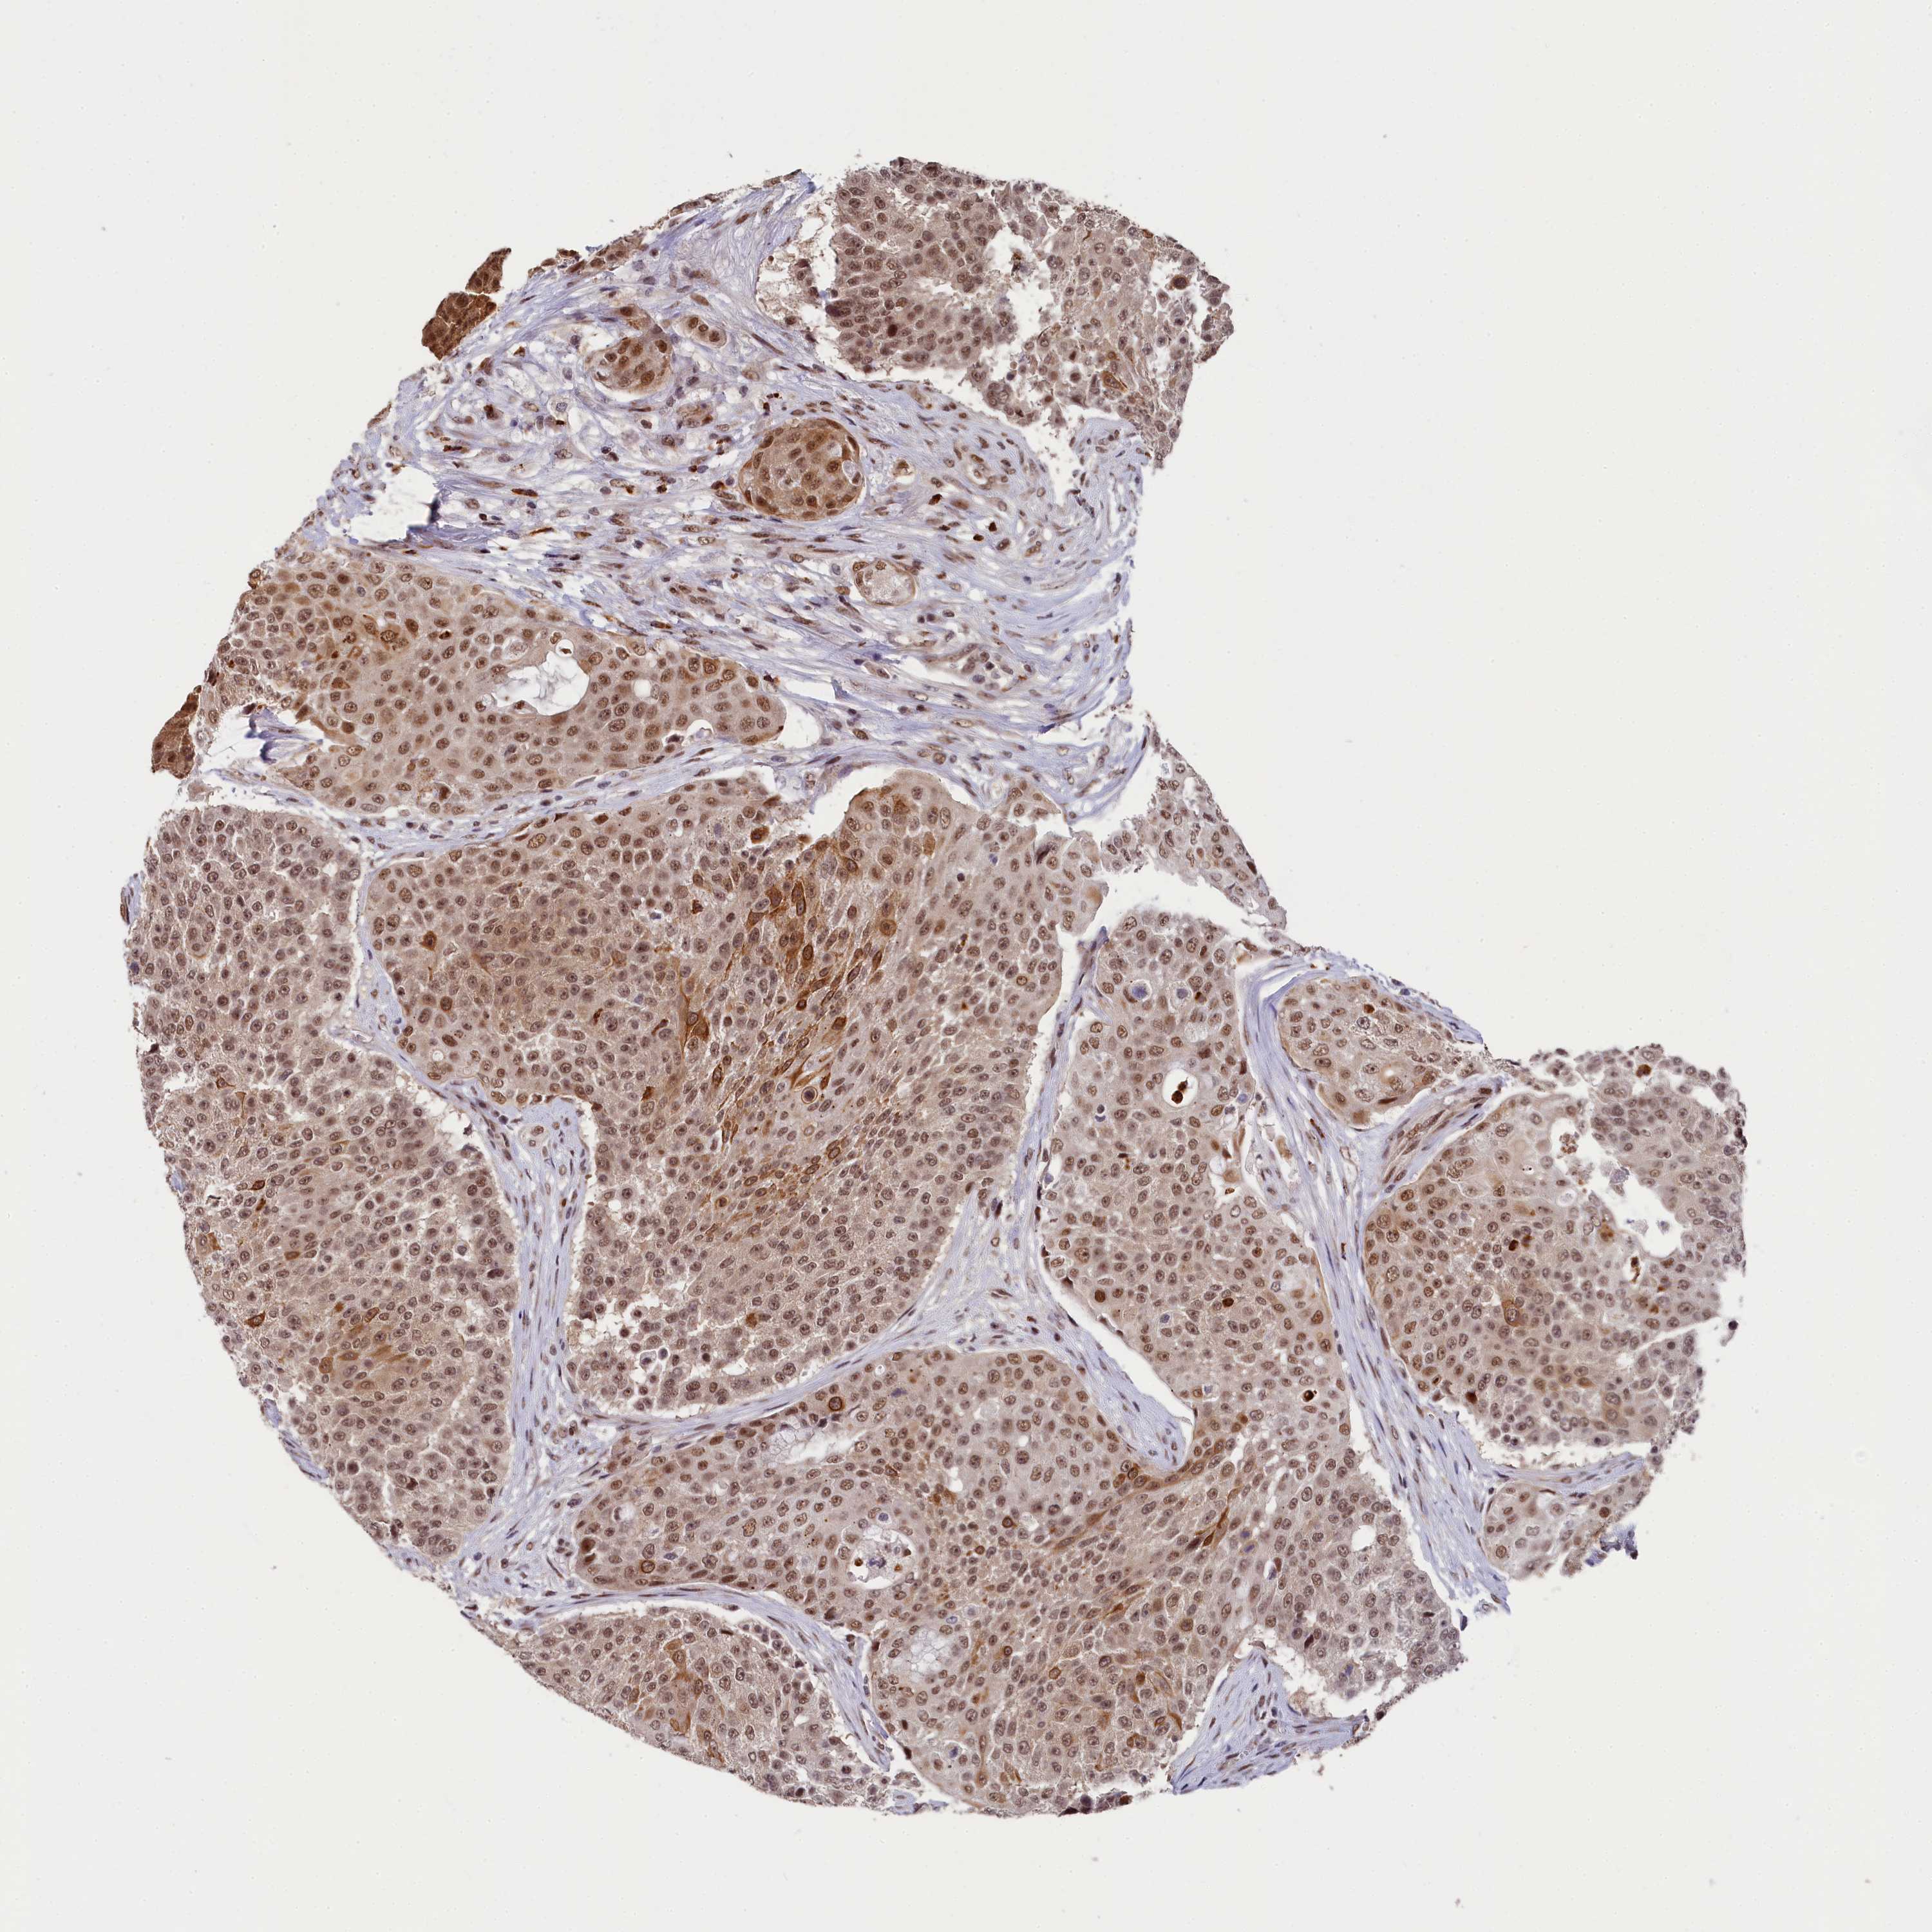

UROTHELIAL CANCER - Protein expressioni

A mouse-over function shows sample information and annotation data. Click on an image to view it in a full screen mode. Samples can be filtered based on level of antibody staining by selecting one or several of the following categories: high, medium, low and not detected. The assay and annotation is described here.

Note that samples used for immunohistochemistry by the Human Protein Atlas do not correspond to samples in the TCGA dataset.

Antibody stainingi

Antibody staining in the annotated cell types in the current human tissue is reported as not detected, low, medium, or high, based on conventional immunohistochemistry profiling in selected tissues. This score is based on the combination of the staining intensity and fraction of stained cells.

Each image is clickable and will lead to virtual microscopy that enables deeper exploration of all samples and also displays staining intensity scores, fraction scores and subcellular localization as well as patient and tissue information for each sample.

Antibody HPA041124

Staining

High

Medium

Low

Not detected

Intensity

Strong

Moderate

Weak

Negative

Quantity

>75%

75%-25%

<25%

None

Location

Nuclear

Cytoplasmic/membranous

Cytoplasmic/membranous,nuclear

Urothelial carcinoma, High grade